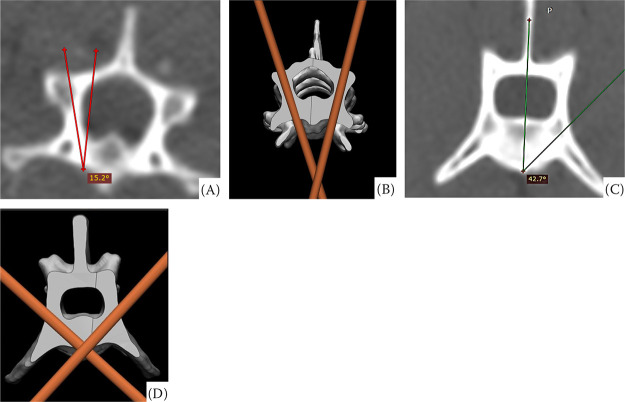

制作10套椎体生物模型和相应的钻孔导轨,评估猫颈(C5-C6)和腰椎(L4-L5)椎体植入的准确性。在随机分配的5组生物模型的右侧和其余组的左侧,使用导针植入光滑的引脚,对侧进行徒手植入。随后,进行了新的层析研究,以测量植入角度。比较不同技术间和不同组间种植前和种植后的角度。与徒手技术相比,导引辅助植入的分散度更低,颈椎的变异系数分别为-1.95和48.9,腰椎的变异系数分别为1.98和9.39。然而,植入前后的角度没有统计学差异,椎节段之间也没有统计学差异(P < 0.05)。在本研究条件下,使用导具不能使猫C5-C6和L4-L5椎体生物模型的植入更加准确。

Ten sets of vertebral biomodels and the corresponding drilling guides were created to evaluate the implantation accuracy in the cervical (C5-C6) and lumbar (L4-L5) vertebrae of cats. Smooth pins were implanted using the guides on the right side of five randomly assigned biomodel sets and on the left side of the remaining sets, with the contralateral side undergoing freehand implantation. Subsequently, a new tomographic study was conducted to measure the implantation angles. The pre-implantation angles were compared with the post-implantation angles between the techniques and among the sets. The guide-assisted implantation exhibited a lower dispersion compared to the freehand technique, with coefficients of variation of -1.95 and 48.9 in the cervical vertebrae and 1.98 and 9.39 in the lumbar vertebrae, respectively. However, no statistical difference was observed between the pre- and post-implantation angles, nor when comparing the vertebral segments (P > 0.05). Under the study conditions, the use of the guide failed to result in more accurate implantations in the C5-C6 and L4-L5 vertebral biomodels of cats.